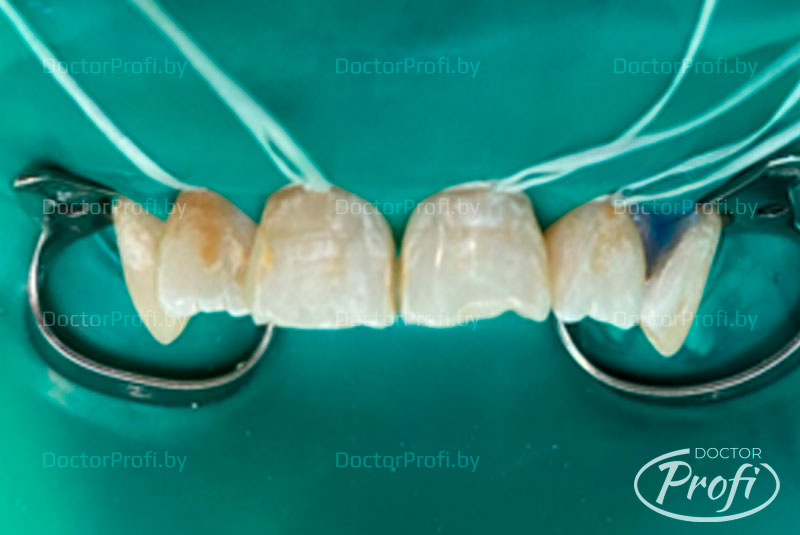

- Процедура микроабразии твердых тканей 12, 11, 21, 22 (“Opalustre”) – 2 сеанса. Продолжение лечения осуществлялось после курса реминерализирующей терапии в течение 1 месяца.

- Эстетическая реставрация 12, 11, 21, 22 с использованием материала Estelite Asteria.